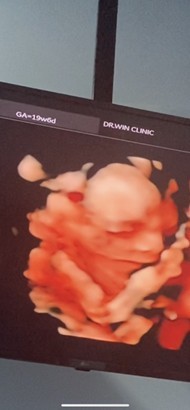

ซาวด์ 4 มิติ ตอน19 W 6Dค่ะ ล่าสุดเมื่อ2วันที่ผ่านมาค่ะ หมอบอกได้ลูกสาวค่ะ